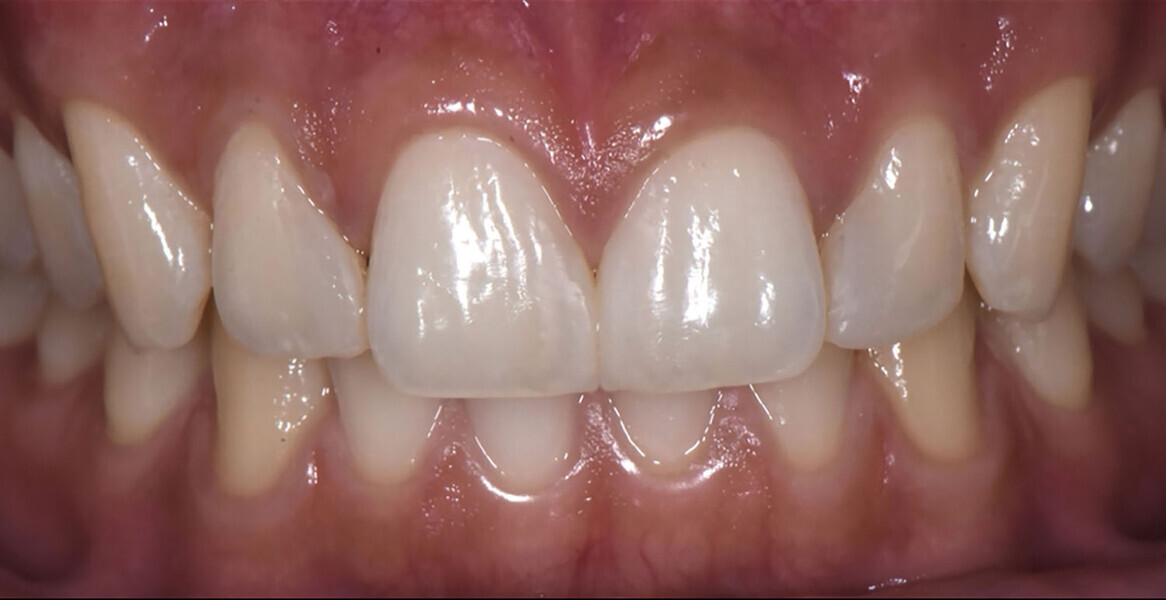

At the six-month follow-up appointment, the patient’s situation was very different to that at the initial consultation. There was proper closure of the interdental gaps and consequent formation of papillary tissue that harmonised the shape of the attached gingiva and of the reconstructed enamel perimeter (Figs. 18–21). In addition, the examination showed no fractures of the restoration or wear, no marginal discoloration or other staining, adequate marginal seal, adequate colour stability and translucency, very good surface structure and anatomical shape, excellent contact points, very good integrity of the teeth and no inflammation.

Fig. 20: Aesthetic result achieved.

Results

The patient was satisfied with the aesthetic accuracy in terms of restored anatomy, the gaps in the interdental space have been resolved. This result gave an implicit added value to the direct restoration technique: micro-invasiveness. The patient did not feel any discomfort during the operative steps, as no significant preparation of the teeth was needed.